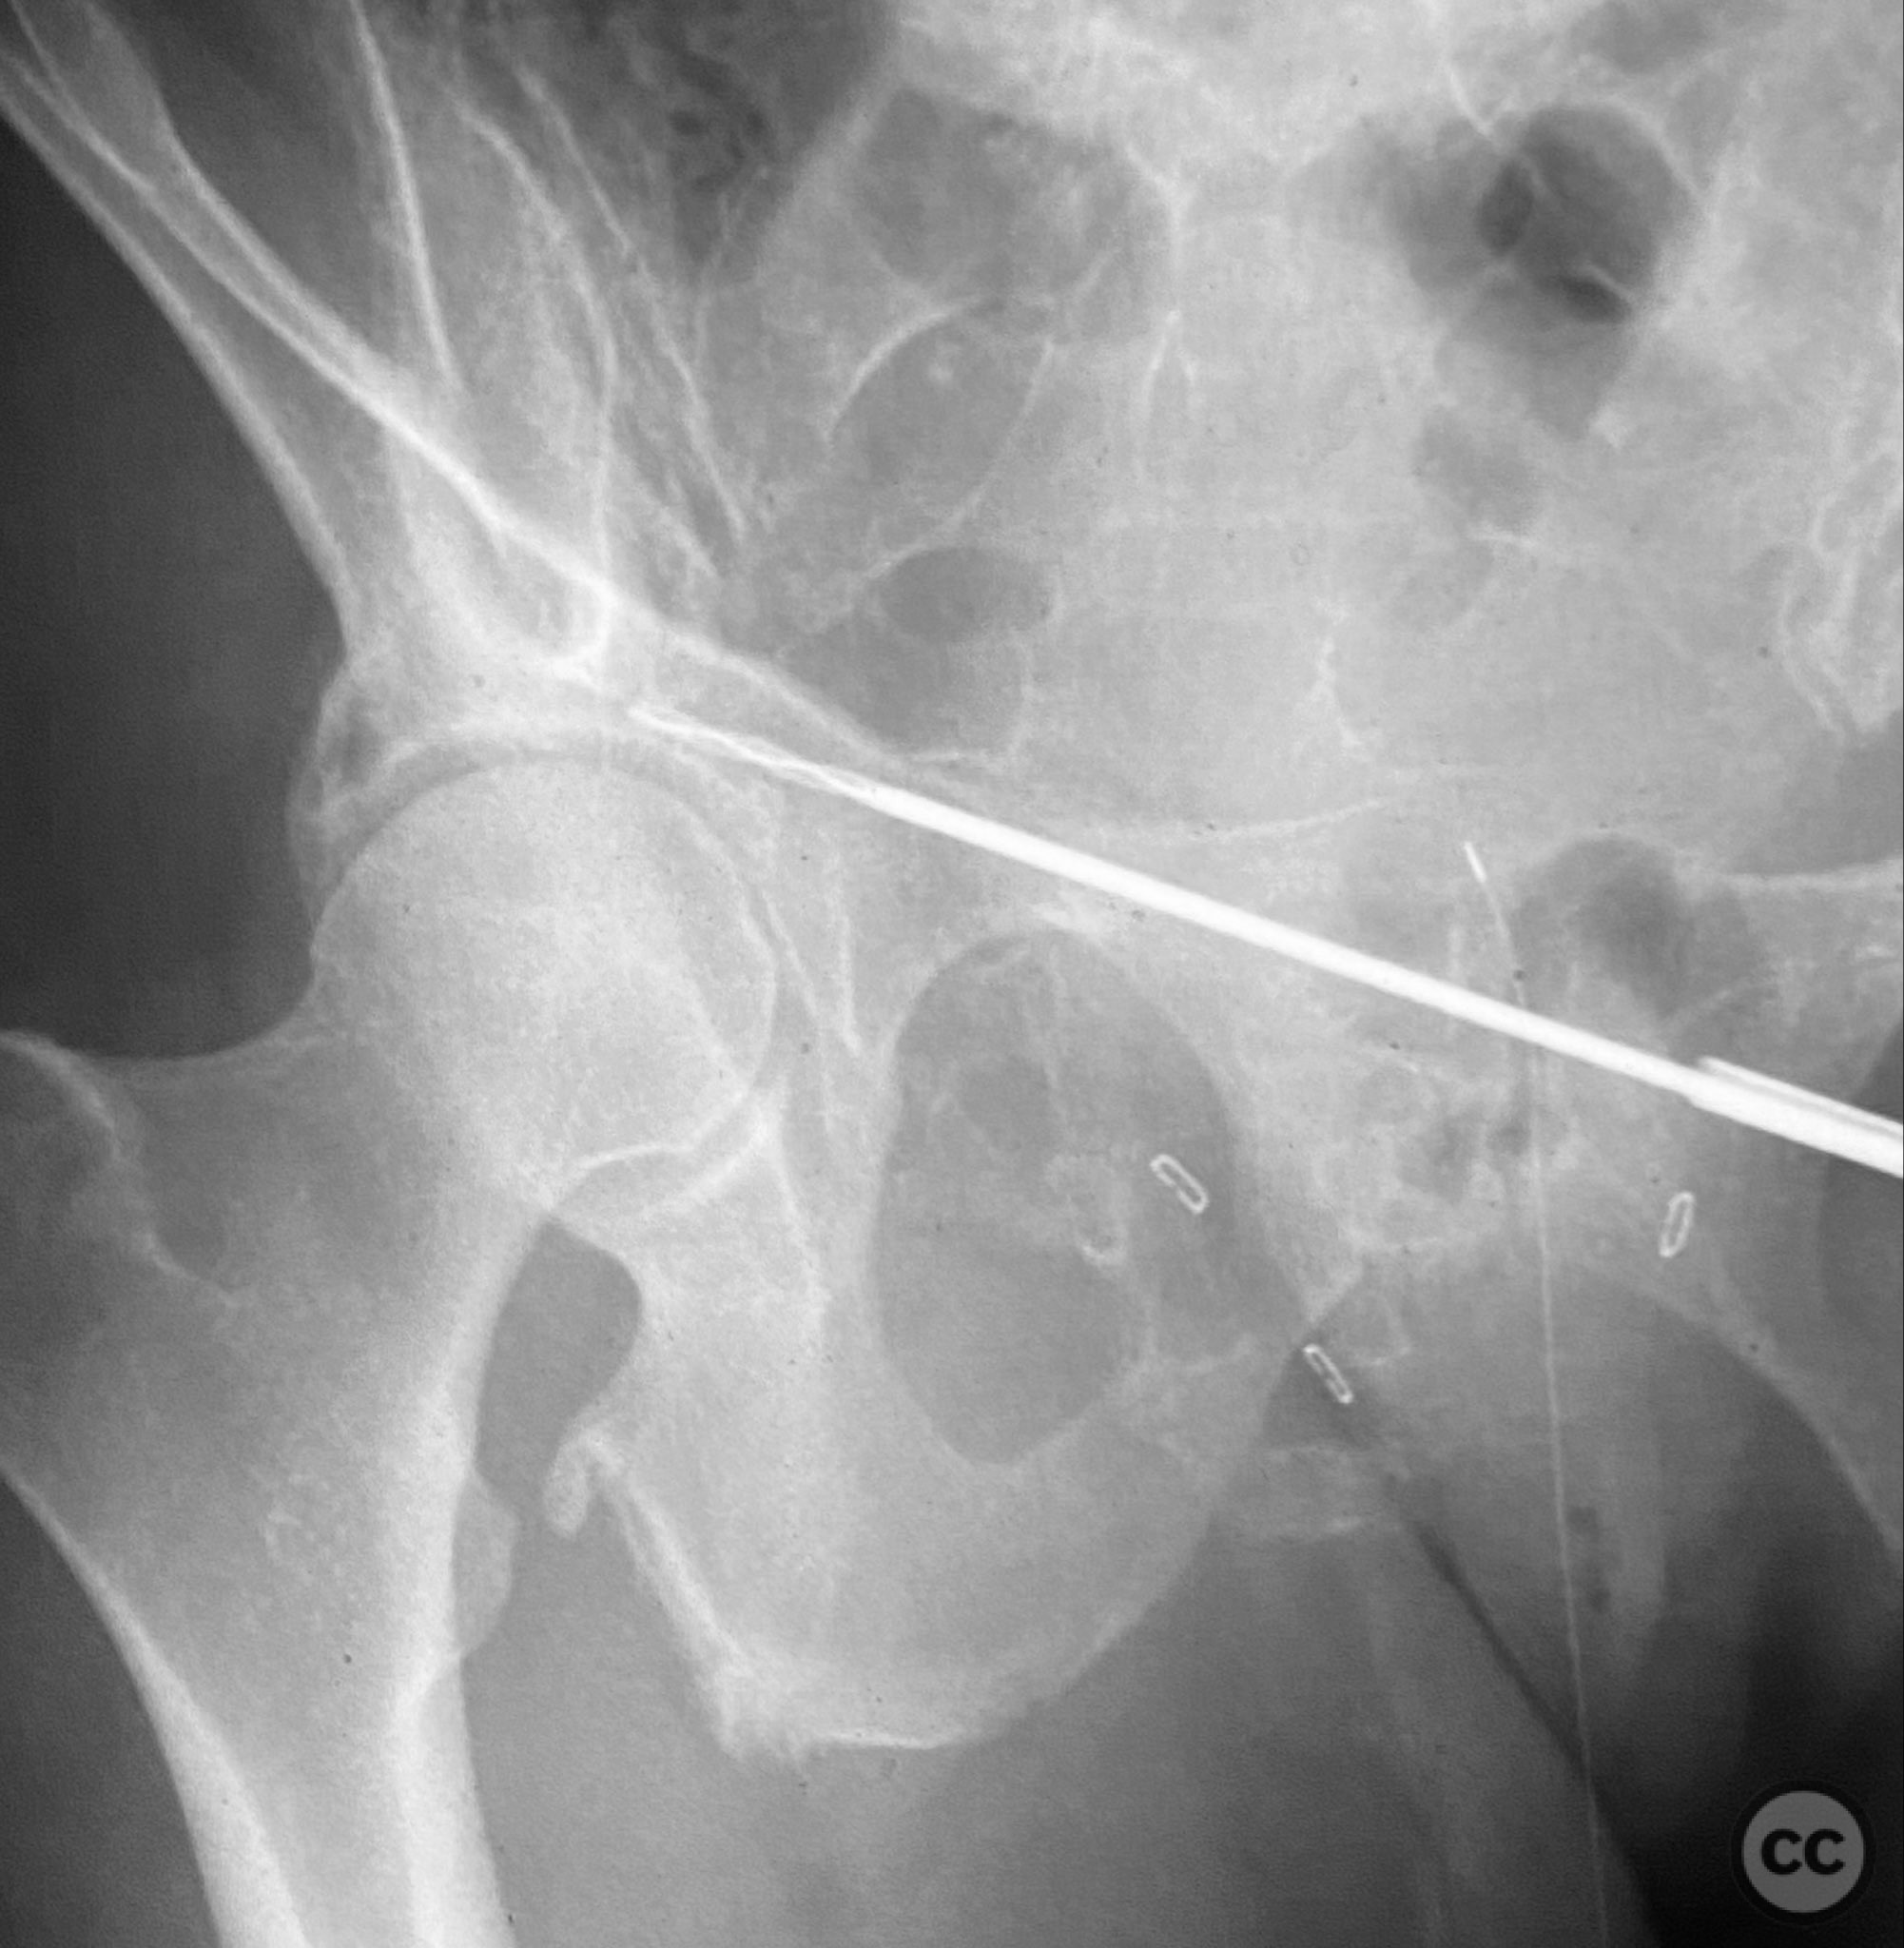

Intraoperatively, a 3.5mm drill was used through a protective sleeve to initiate the screw pathway across the superior pubic ramus. Due to poor bone quality, a 2.5mm drill was subsequently employed; however, resistance was encountered as the drill tip engaged the dense cortical apex of the anterior acetabular wall. The drill became lodged in this region. To avoid drill breakage, manual extraction using pliers was considered; however, the surgeon elected to carefully deflect and advance the drill manually, successfully completing the pathway. Screw length was measured directly from the embedded drill tip. A 4.5mm cortical screw was then inserted trans-symphyseally along the prepared medullary canal, achieving stabilization of the unstable ramus fracture. Postoperative CT confirmed appropriate screw trajectory and demonstrated the dense cortical bone at the anterior acetabular wall where the drill tip had engaged.

Postoperative protocol:   Early mobilization as tolerated with protected weight bearing, avoidance of forced hip abduction or external rotation for 6 weeks, and progressive increase in activity as pain allows.

Orthopaedic implants used:   4.5mm cortical screw